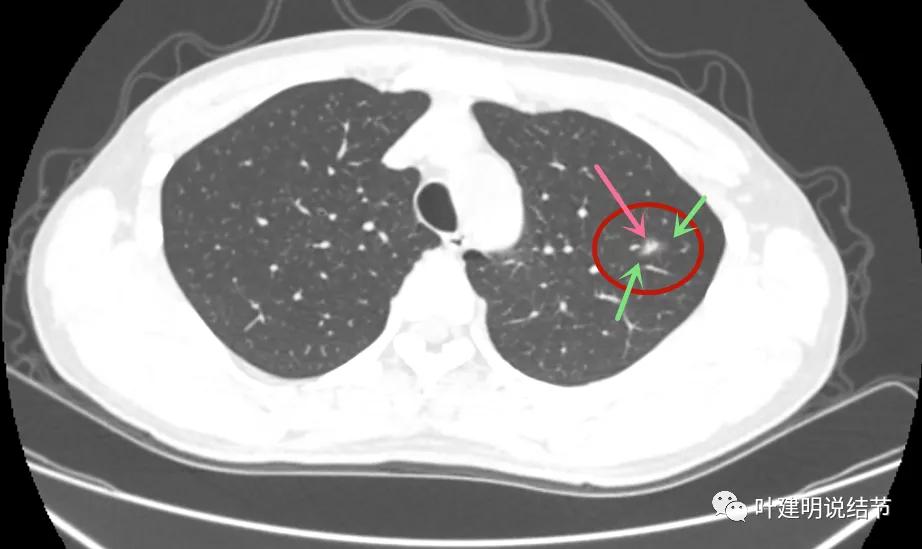

病灶1:左上叶结节是混合磨玻璃,但磨玻璃部分密度很低,实性部分密度高,感觉偏散,没有明显收缩力,瘤肺边界模糊不清

病灶2:左下叶极淡的磨玻璃结节,中间似有空泡或偏低密度,但血管似乎有点走向病灶的样子

病灶1几乎没什么变化,实性部分范围感觉略大,显模糊。我考虑是因为薄层的关系,不是病灶有明显变化,轮廓仍是不清的

病灶2仍是极淡的,但也没有消失,有微血管贴边走行,间隙不清,此灶倒是要考虑不典型增生之类的范畴的病灶,虽然小又淡。

病灶1没有明显变化

病灶2也仍在,微血管征仍较明显,病灶本身淡而小

我的意见:病灶1考虑慢性炎伴纤维增生可能性大;病灶2考虑不典型增生可能性大;病灶3可能是肺泡上皮增生或不典型增生,从薄层看也可能是原位。但均可先再随访复查,建议半年后左肺上叶靶扫描加重建以观察主病灶形态仔细。病灶2与病灶3近期没有风险,可年度常规复查。